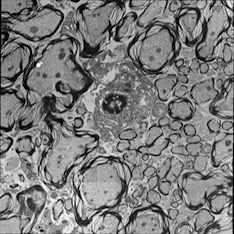

Correlative microscopy is an integration of different microscopy technologies including conventional light, confocal and electron transmission microscopy [6]. Correlative microscopic images usually involve linear or non-linear distortions which are caused by the differences between imaging systems and processing steps. Therefore, the first step of most correlative microscopy based applications is to do registration between two or more microscopic images. An example of correlative microscopic images is presented in Fig. 1.

Refer to caption

(a) Confocal Microscopic Image

(b) Resampling of Boxed Region in Confocal Image

(c) TEM Image

Figure 1: Example of Correlative Microscopy. The goal is to align (b) to (c).